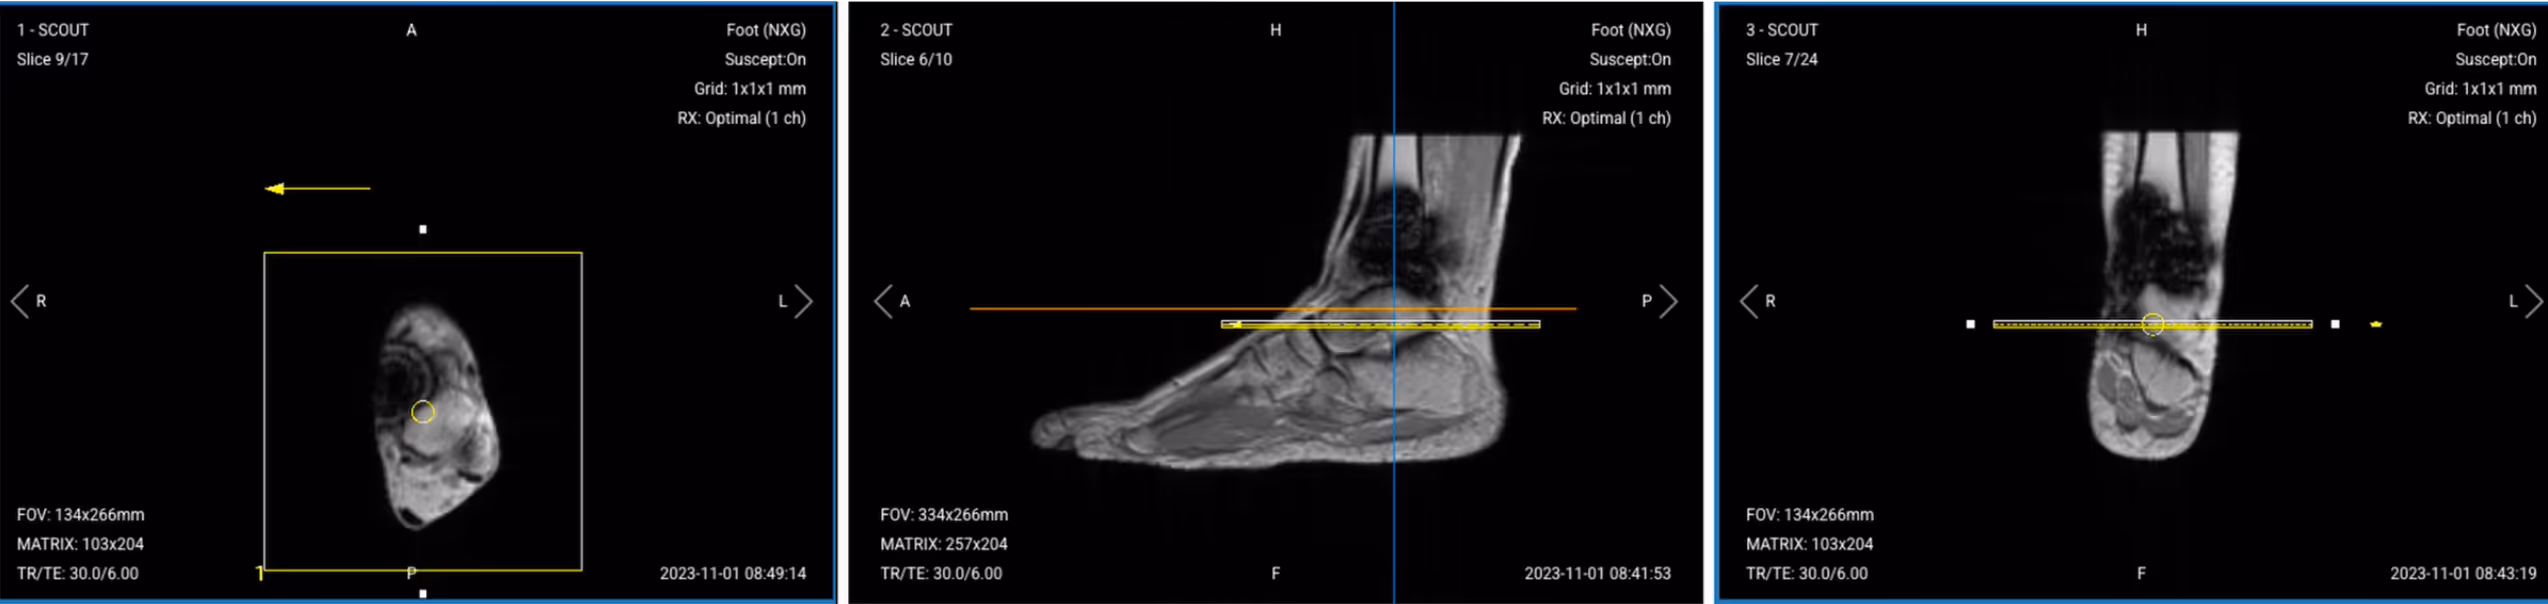

1. Sagittal T1 TSE

Correct Planning:

Correct slice planning of Sagittal T1 TSE

Planning Instructions:

• Use the medial and lateral malleoli as your anatomical references.

• Align the slices as follows:

• Axial localizer: Angle slices perpendicular to the malleoli and center over the ankle joint.

• Sagittal localizer: Center the slice package over the ankle.

• Coronal localizer: Ensure slices are parallel to the tibial bone.

• Use appropriate geometry parameters:

• Slice number: Enough slices to cover the ankle from medial to lateral (20–25 slices).

• Slice thickness: 3 mm for high resolution to visualize tissues around the metal.

• Slice gap: 0.3 mm (10% of slice thickness) to maintain continuity.

• Set the fold-over direction (phase encoding) to anterior–posterior (AP) to steer wraparound artifacts away from the implant.